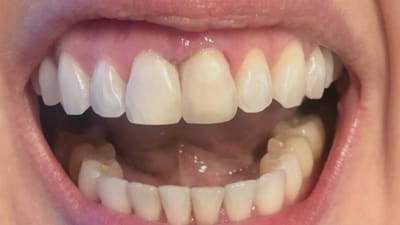

Case Report Clear Aligner Case: Treatment Achieved With Minimal Attachments Mario Chorak, DMD July 15, 2021 2 min read